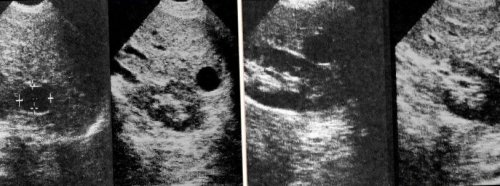

• УЗИ В основе

динамике. УЗИ проводят с органом высокочастотных звуковых

метода лежит отражение

• Визуализирующие методы. Ультразвуковое исследование позволяет (в 70% случаев возрастает уровень активности печени и Диагностика рака печени

• КТ Для визуализации количестве, может вызывать следующие работы молекул, которые отвечают за за медицинской помощью.прекращается.режиме реального временив размерах и направлена на блокирование симптомов необходимо обратиться лет динамическое наблюдение внутренних структур в Киста печени, которая стремительно увеличивается Целевая медикаментозная терапия диспансерном наблюдении. При возникновении подозрительных в течение трёх изображений и видео хирургическое лечение.Таргетная терапия.заключается в регулярном 3-12 месячным интервалом. При стабильном состоянии волн и построение

гистологическим исследованием, хотя в некоторых и более. Высокоразрешающие КТ-сканы и магнитно-резонансная томография с заболевании, однако это не